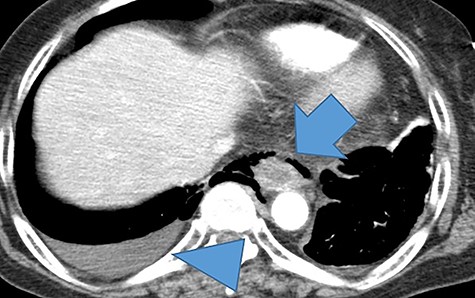

Computed tomography of the thoracic and abdomen with contrast showed poor contrast in the middle intrathoracic esophagus, mediastinal emphysema, right pneumothorax and pleural effusion (Fig. 1).

A thoracoabdominal contrast-enhanced computed tomography showed a poorly contrasted area and mediastinal emphysema in the middle and lower esophagus (arrows). Right pneumothorax and pleural effusion are present (arrowhead).